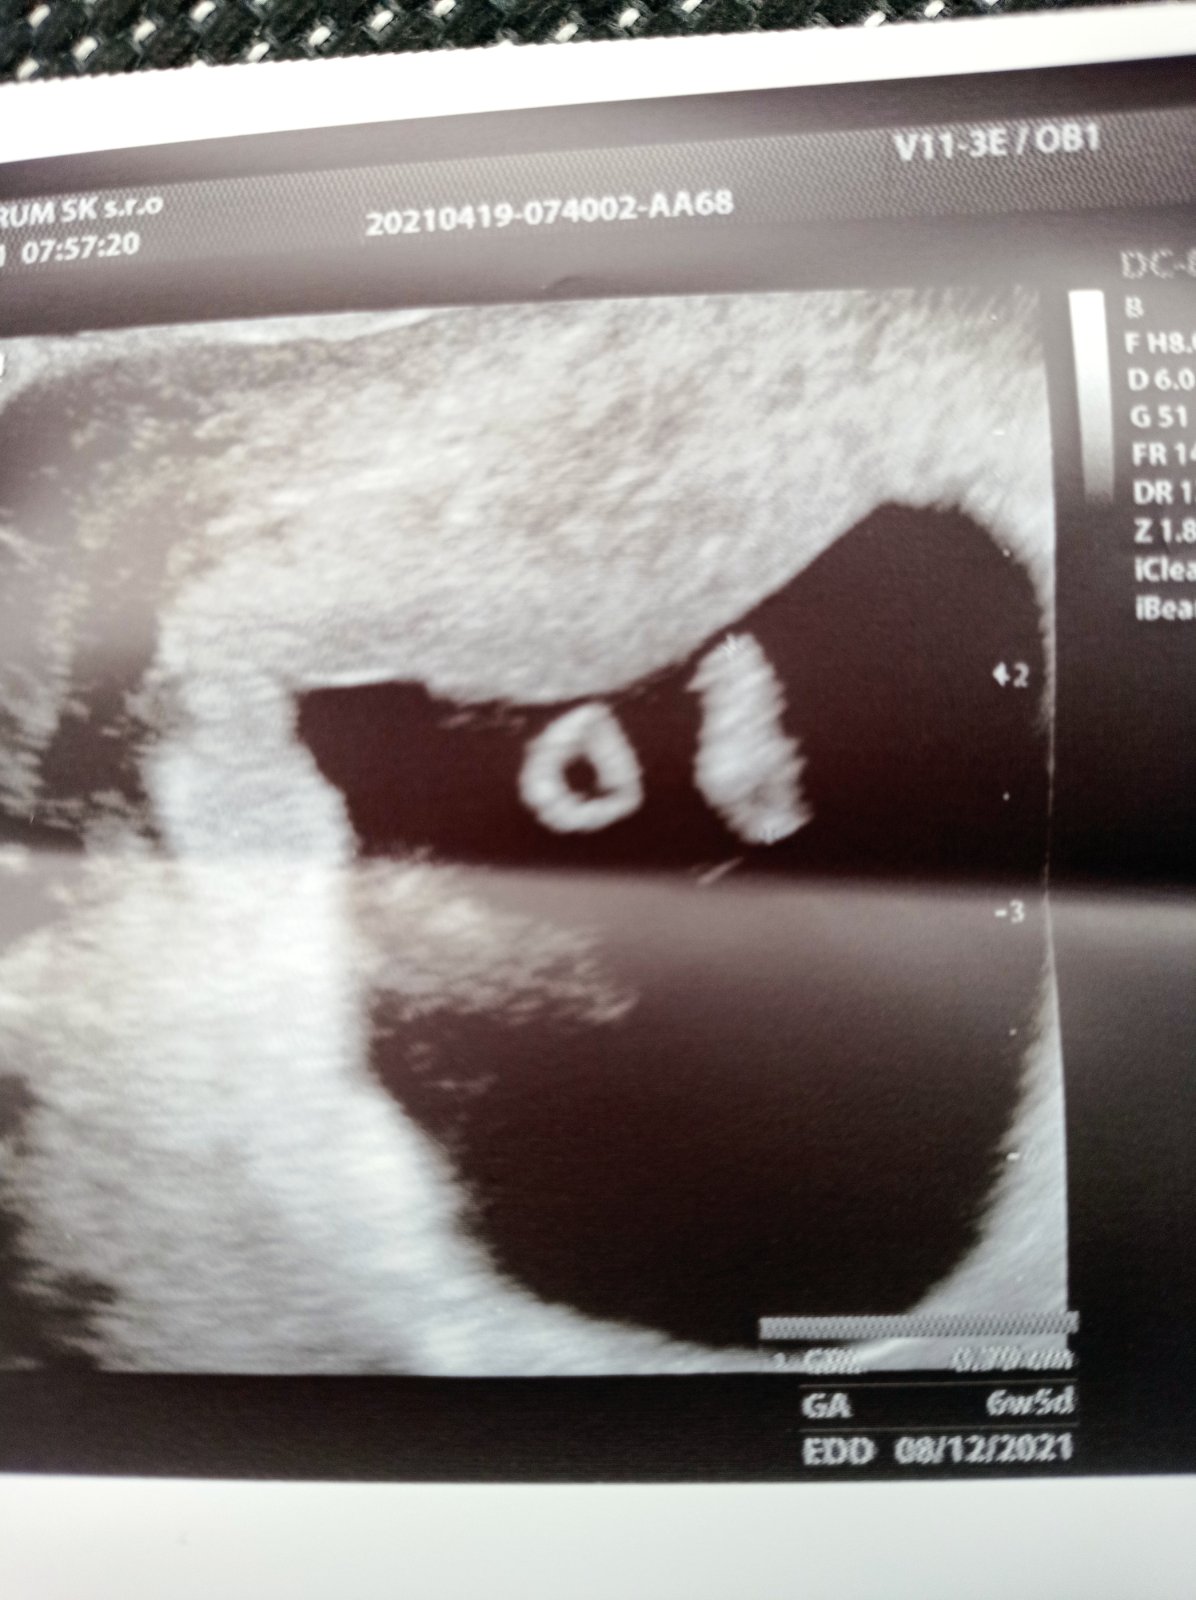

Ahojte. Pred časom som sa tu tiež tešila z pozitívneho testu. Dnes som bola u Dr. a podľa sona 6+5 (podľa MS 7+6). Mala som zrejme o týždeň posunutú ovuláciu čo aj sedí podľa toho že mi neskôr začali vychádzať pozitívne testy. Teším sa veľmi. Už nám bije aj srdiečko, ale to nekonečné čakanie... V decembri som mala potrat. Už len nech rastie fazuľka moja. Držím Vám všetkým palce.